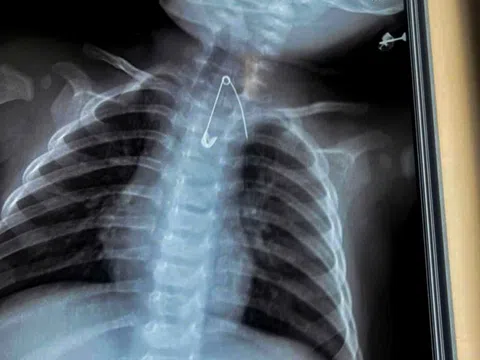

Cứu sống hai em bé nuốt kim băng và cây kẹo mút

Ngày 8-1, Bệnh viện Sản Nhi Cà Mau cho biết các bác sĩ vừa tiếp nhận và xử trí thành công hai trường hợp...